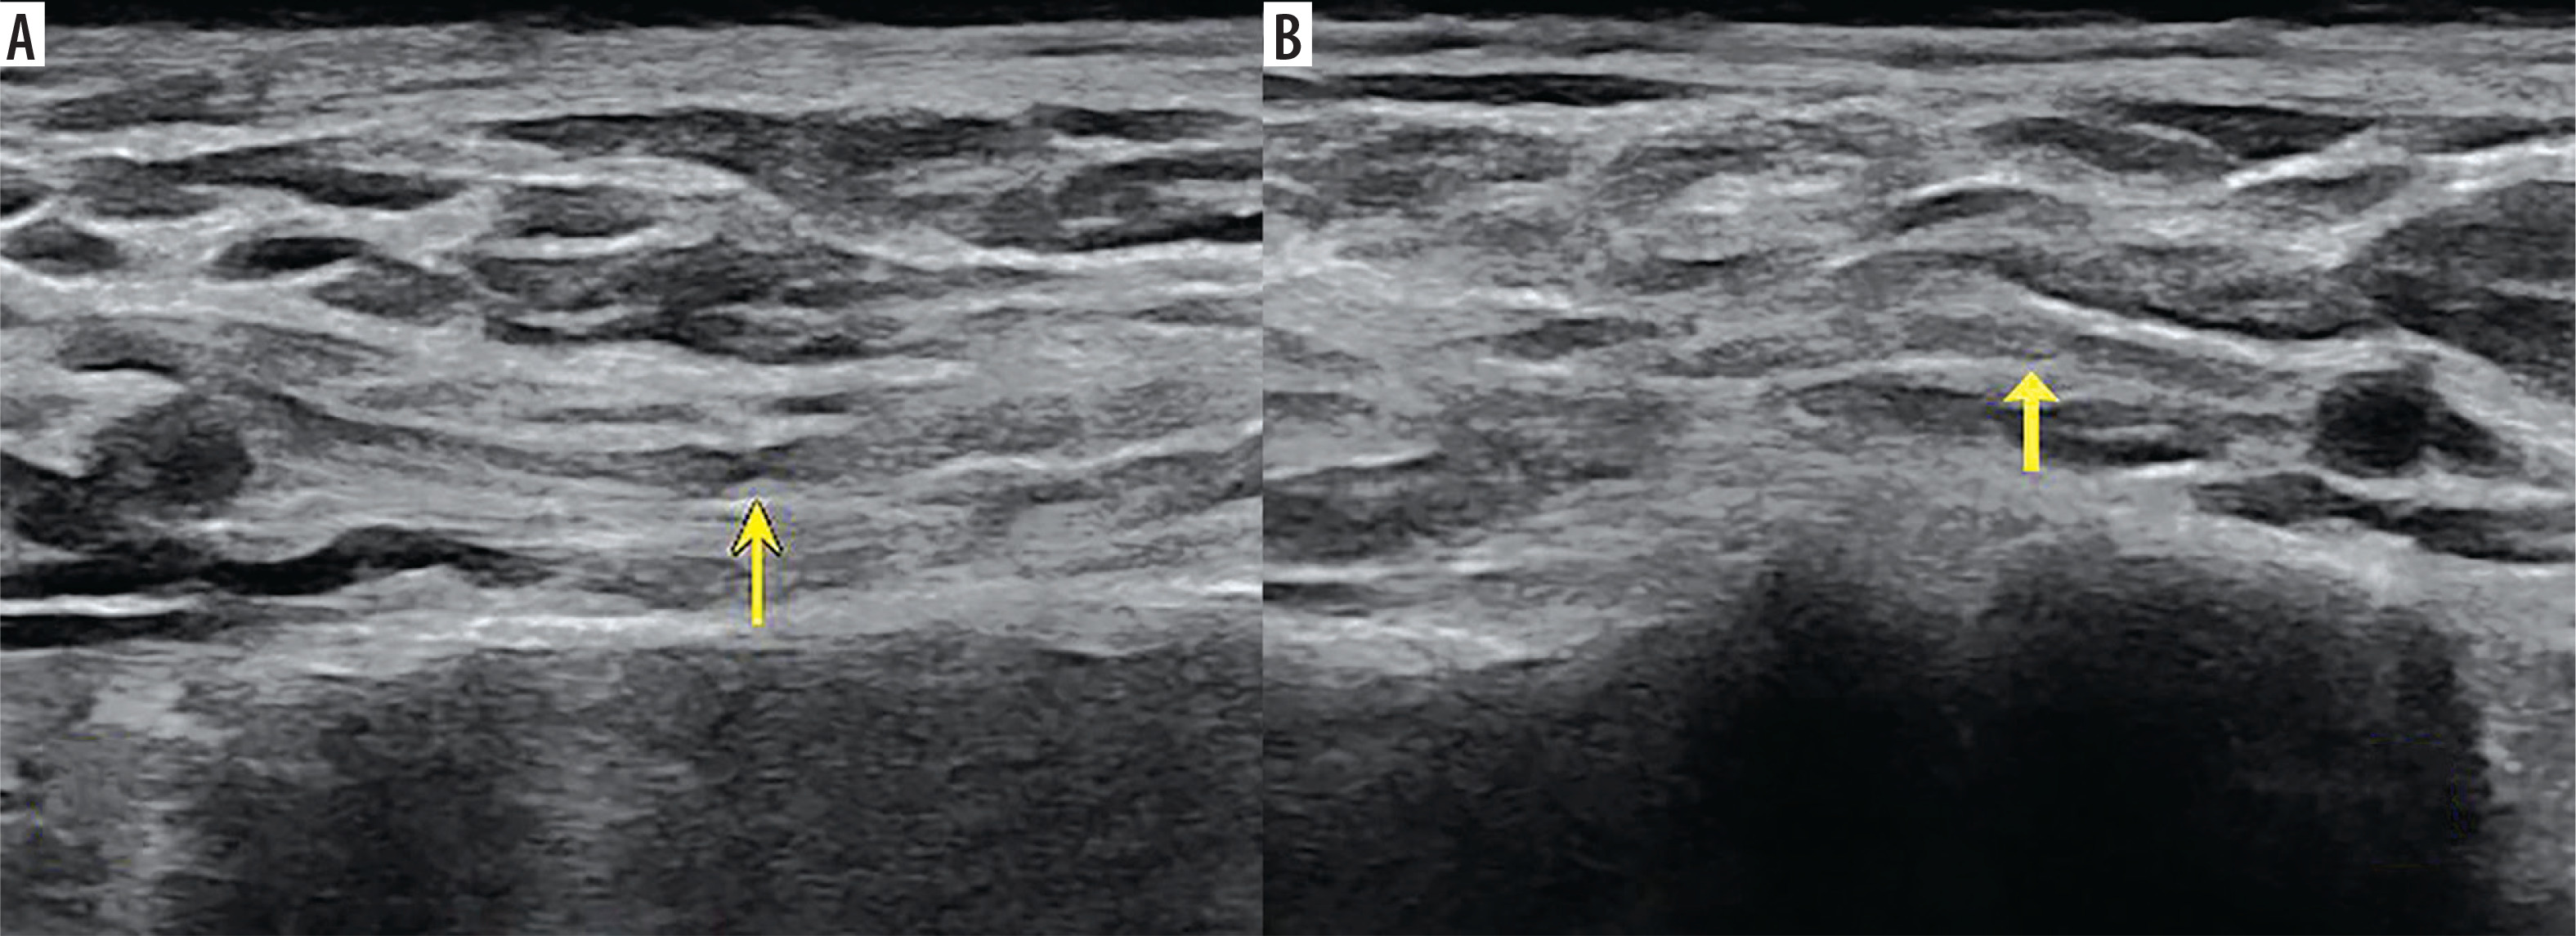

Figure 2

High-resolution ultrasound image of LTN torsion with an ”hourglass-like” constriction sign – marked with arrow (A) with comparison to the asymptomatic side (B) in 50-year-old patient with Parsonage-Turner syndrome. Images obtained by author with a 3-19 H linear probe of the Alpinion XCube90